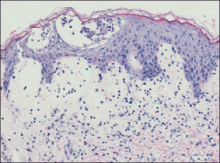

Histologic examination revealed intraepidermal neutrophils with focal aggregation into subcorneal pustules. Papillary dermal edema was prominent with a superficial perivascular and interstitial inflammatory infiltrate of lymphocytes, neutrophils, and numerous eosinophils (Figure 2). These findings were consistent with acute generalized exanthematous pustulosis (AGEP). All blood cultures were negative. Within a few days the edema and erythema subsided, leaving desquamating erythematous patches. The patient’s other medications included simvastatin, citalopram, levothyroxine, hydrocortisone cream, celecoxib, and pramipexole, all of which she had been taking for at least 3 years. She also was taking oxycodone hydrochloride and warfarin, which were initiated after the knee replacement. Based on the patient’s history as well as the clinical and histologic appearance, she was diagnosed with daptomycin-induced AGEP.